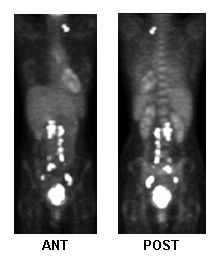

PET whole body

Test

Used to evaluate local/metastatic spread and aid treatment planning.[98][103]

Detection of recurrence: sensitivity 80%, specificity 100%.[105][Figure caption and citation for the preceding image starts]: Fluorodeoxyglucose-PET for treatment planning, metastatic activityFrom the collection of Neil S. Horowitz, MD; used with permission [Citation ends].

Result

may show increased metabolic activity in areas of involvement